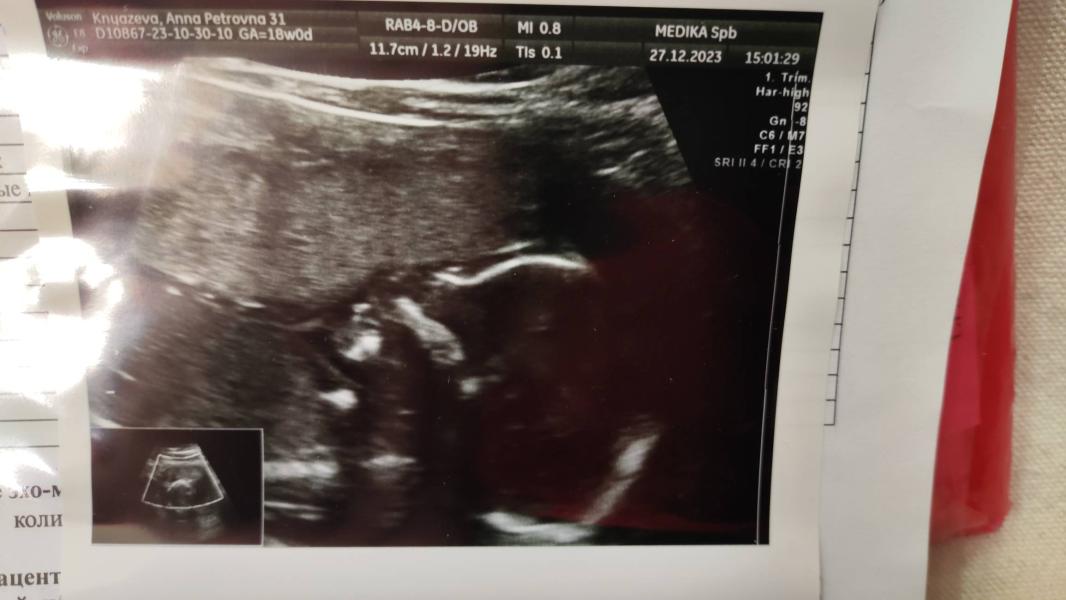

Сделала УЗИ, сказали будет мальчик: переживаю, перепутали или нет, срок 17,6, нет перегородки

post image 2

Сделала узи, сказали мальчик 🚙

Надеюсь это точно, не перепутали и ничего не отвалится к следующему узи😂

Немного смущает, что не нашли полость прозрачной перегородки, по узи сейчас 17,6, надеюсь просто чуть позже, что это нормально